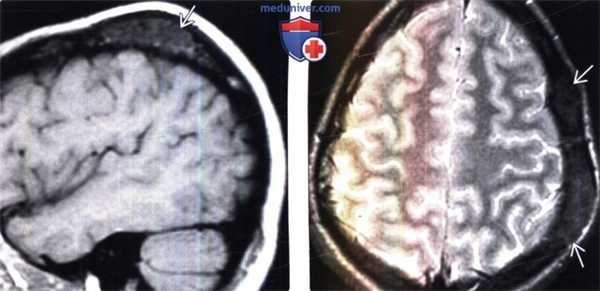

(Слева) МРТ, Т1 -ВИ, сагиттальный срез: у юноши 77 лет с медленно увеличивающейся в размерах «шишкой на волосистой части головы» определяется объемное образование свода черепа, которое имеет умеренно гипоинтенсивный сигнал.

(Справа) МРТ, Т2-ВИ, режим подавления сигнала от жира, аксиальный срез: у этого же пациента отмечается, что поражение имеет слегка неоднородный гипоинтенсивный сигнал.в) Дифференциальная диагностика фиброзной дисплазии:

(Слева) МРТ, постконтрастное Т1-ВИ, сагиттальный срез: у этого же пациента определяется два поражения свода черепа, умеренно интенсивно, но гетерогенно накапливающие контрастное вещество.

(Справа) МРТ, постконтрастное Т1 -ВИ, режим подавления сигнала от жира, аксиальный срез: интенсивное, но гетерогенное контрастное усиление поражений. Данные рентгенологические признаки характерны для активной фиброзной дисплазии.1. Общие характеристики фиброзной дисплазии: